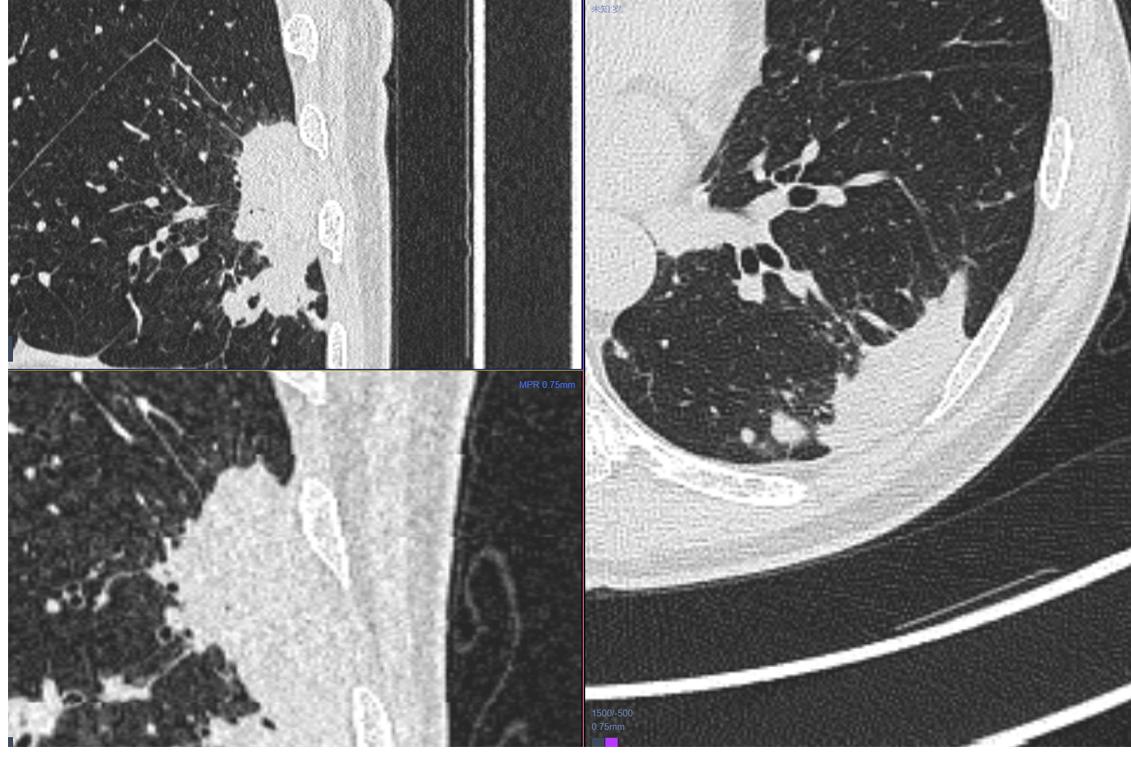

2.女性 56岁 体检发现右肺上叶前段占位,无特殊不适。

啥也不说了,实性软组织结节,大小约1.9cm×1.5cm,和病例1一样,该有的征象都有了……而且还出现支气管的截断、鼠尾征这些典型的特点。但是有没有不太符合的,我们在诊断的时候还是留了一手,建议活检除外感染性病变。